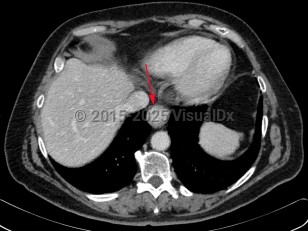

Esophageal carcinoma

Synopsis